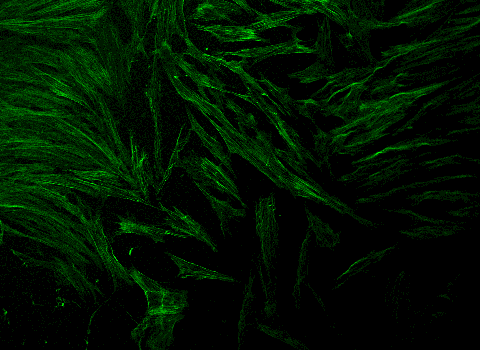

La ingeniería regenerativa es un campo nuevo y emocionante que se define como la convergencia de los avances en la ciencia e ingeniería de materiales, células madre y biología del desarrollo, ciencias físicas y la aplicación clínica para desarrollar herramientas escalables y confiables que permitan la regeneración ó reconstrucción de tejidos complejos y órganos. Puede considerarse un campo que busca facilitar la implementación de la medicina regenerativa para todos.

Con este objetivo, profesores de la Escuela de Ingeniería McCormick y de la Escuela de Medicina Feinberg convergen para participar en investigaciones y educación a través del Instituto Querrey Simpson de Ingeniería Regenerativa de la Universidad Northwestern (QSI RENU), que liderará la iniciativa para desarrollar y traducir tecnologías transformadoras que capaciten a nuestro cuerpo para sanar.